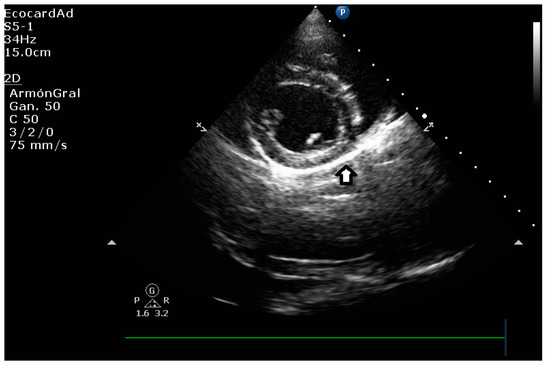

5.1.2. E-Point to Septal Separation or EPSS: An Echocardiographic Parameter for Accurate Assessment of Left Ventricular Performance